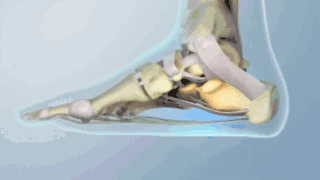

足弓的功能就像弓(就是射箭的弓),足底筋膜就像弓的弦。“弓弦”的张力保持拱的形状。但每次你走一步,随着你下肢肌肉的牵拉,“弓弦”不断收紧和伸展,把你的身体像箭一样射出去。可当拉伸太硬和太频繁,这根“弦”被激怒了,然后它就会像“弹棉花”一样,“咯嘣”一下弹在你的脚上!这时就发生了困扰大家的跖筋膜炎,俗称足底筋膜炎。